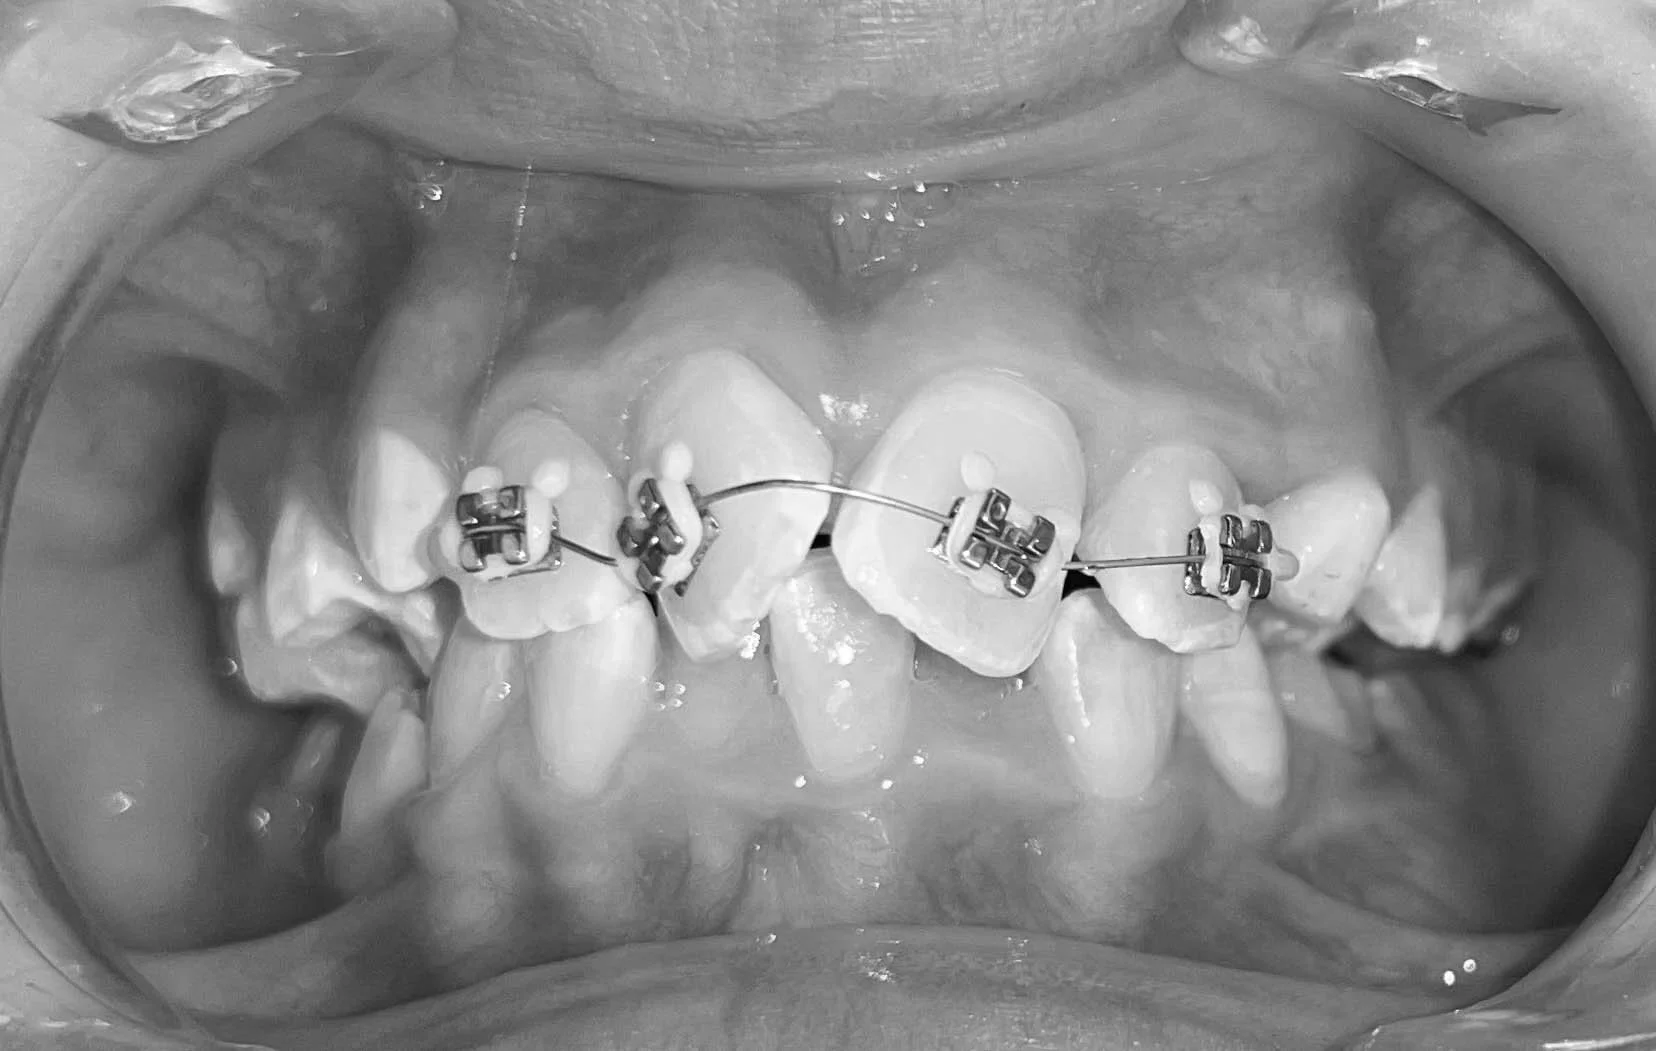

Première phase : l’orthodontie précoce (6–9 ans)

La première phase vise à guider la croissance des mâchoires et à corriger les déséquilibres susceptibles de s’accentuer avec le temps.

Objectifs

• Favoriser un bon développement des mâchoires

• Créer l’espace nécessaire à l’éruption des futures dents définitives

• Corriger certaines habitudes orales (respiration buccale, succion du pouce, etc.)

• Limiter le risque de malocclusions complexes

Méthodes utilisées

• Appareils fonctionnels

• Élargisseurs de palais

• Appareils fixes ou amovibles adaptés aux besoins de l’enfant

Cette phase est généralement courte et ciblée, et contribue à simplifier la prise en charge orthodontique à l’adolescence.